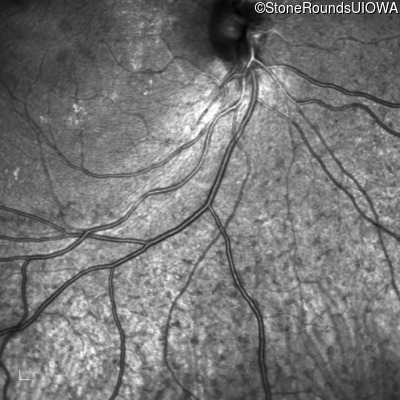

Infrared Fundus Photograph - Right - 20/25 -1

Exemplar